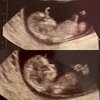

Cudownie ❤❤❤❤Dziewczyny jestem po drugiej wizycie, dzisiaj 10+0![]()

Serce bije, nosek już widoczny, przezierność wydaje się prawidłowa. Ulgaaa![]()

Na pierwszym zdjęciu macha ręką, na drugim ładnie widać budowę głowy![]()

te Nasze dzieci jak na drożdżach rosnąDziewczyny jestem po drugiej wizycie, dzisiaj 10+0![]()